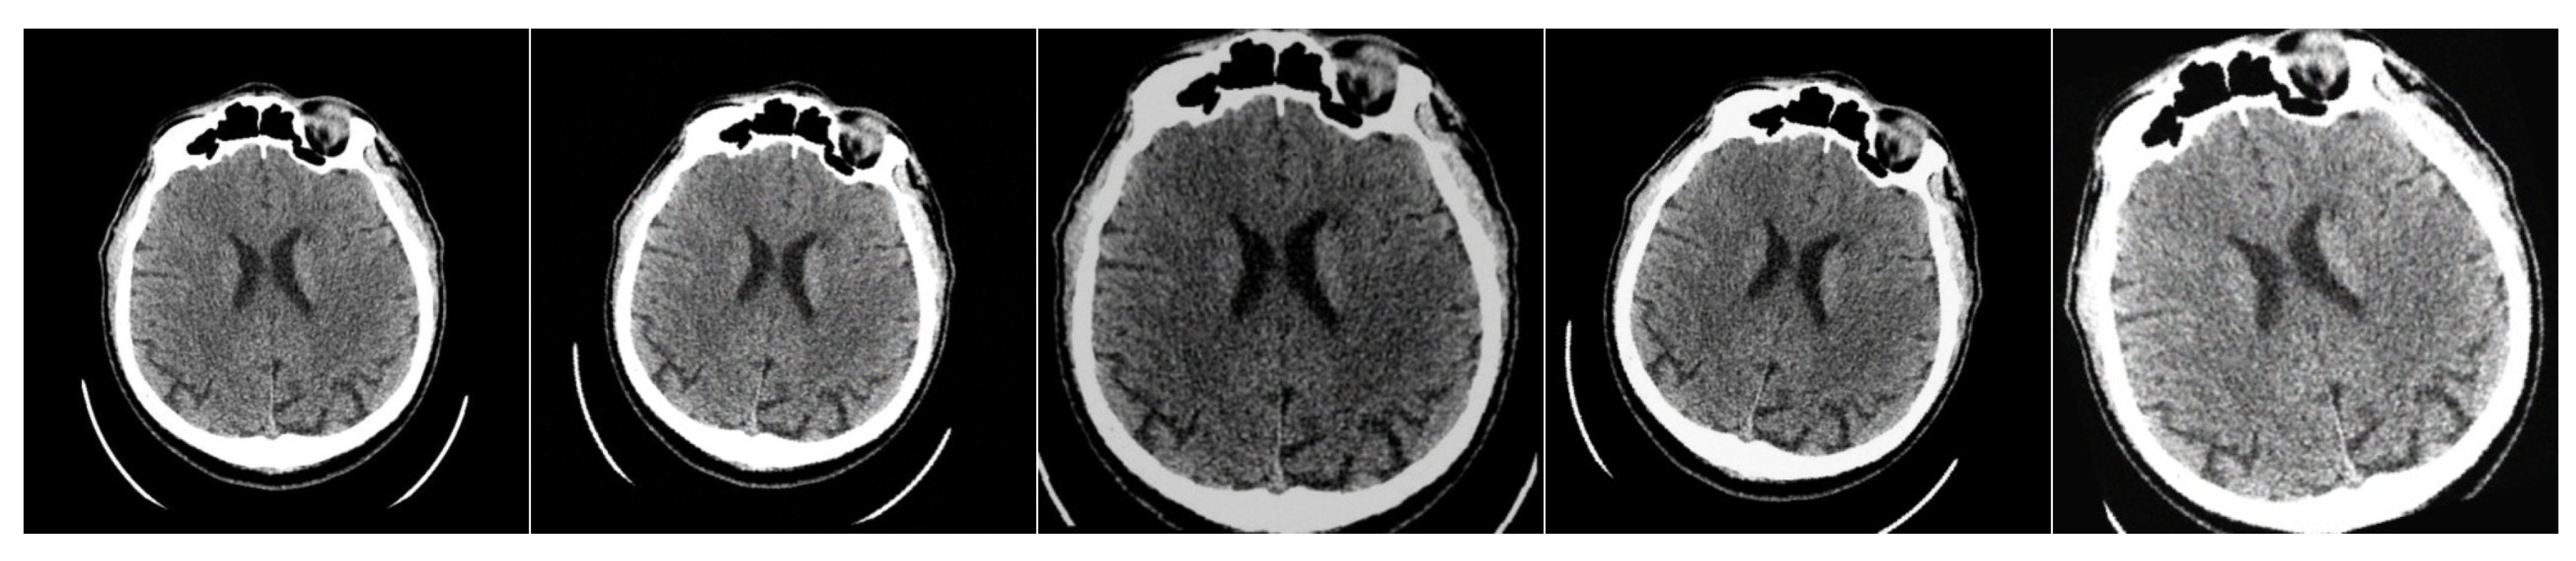

For training our lightweight image preprocessing model, we slightly modified the original dataset to create a synthetic set of medical image pairs from the CPAISD dataset. In other words, we apply soft augmentations [66,67] to the original dataset to generate a “slightly degraded” version of the images. Our goal is to change the image while maintaining its structure and meaningful information. The important point is that we also used for augmentation all the simulated image transformations in our domain, accessible by changing all the filter settings and all the filter types from the LFIEM/UNIFI articles (including dedicated discrete sharpening and contrast filters, linear transformations, convolutions with a universal kernel, and approximations of exposure variation)—that is, covering a wide range of optical transformations, after which we identified the optimal combination of filters and then trained this limited range of filters to correct a wide variety of distortions. Thus, during training, we use the original images as target images and the augmented ones as source images. We apply a random combination of the following transformations: light blur (with sigmaX and sigmaY in the range from 0 to 0.20), Gaussian noise ( m e a n = 0 , var randomly chosen from 10 to 50), CenterCrop (central crop to a resolution between 400 × 400 and 512 × 512 , followed by resizing to 512 × 512 ), rotation by a small angle (from 10 to 10 degrees), as well as contrast and brightness adjustment (in the range from 20 % to + 20 % ). The transformation applied and its strength are selected randomly within the defined probabilities and limits. An example of the applied transformations is shown in Figure 6.